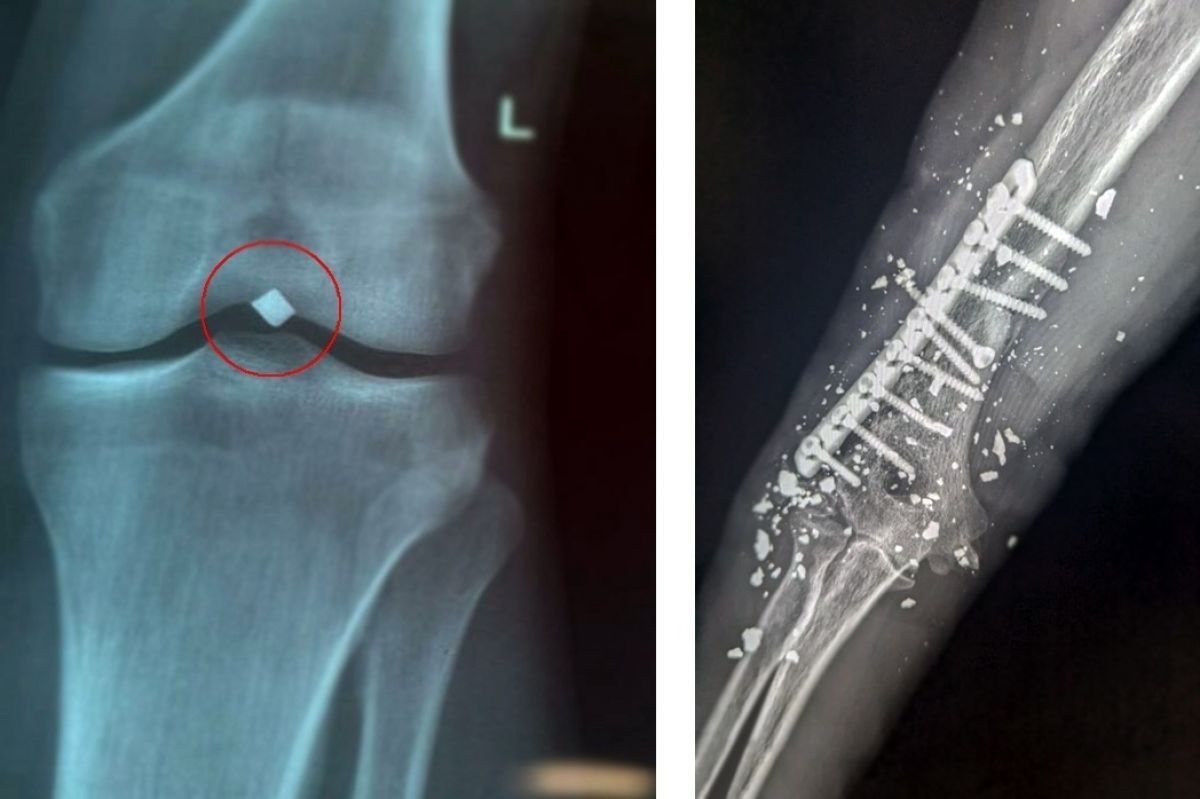

Врачи Рязанской ОКБ спасли конечности двум пациентам, получившим ранения. Подробности рассказала пресс-служба медицинского учреждения.

Один из пациентов - 22-летний парень. В июне 2025 года он получил серьезное ранение осколком - пробил надколенник насквозь, прошел через полость коленного сустава и застрял всего в паре миллиметров от крупного сосудисто-нервного пучка нижней конечности. Пациента беспокоили постоянные боли в области инородного тела. Осколок оказывал давление на нерв, вызывал стойкий дискомфорт и нарушение функции левой нижней конечности.

По словам сердечно-сосудистого хирурга Вячеслава Карпова, выяснилось, что осколок лежал прямо на стенке подколенной вены и практически пролабировал ее, создавая прямую угрозу жизнеугрожающего кровотечения. Операция прошла успешно, осколок был благополучно и аккуратно удален.

Второй пациент поступил в ОКБ с тяжелой травмой правого плеча, полученной в результате минно-взрывного ранения в ноябре 2024 года.

Сразу же после травмы мужчине провели экстренную операцию — первичную обработку раны и накостный остеосинтез плечевой кости. Однако возникли осложнения: появились симптомы повреждения лучевого нерва и началось нагноение вокруг имплантированной металлической конструкции. В течение проводимого лечения ситуация осложнилась формированием хронического свища с постоянным выделением гноя в области фиксации металла. Пациента мучили сильные боли. Сильные боли.

Результаты исследования подтвердили наличие глубокого воспалительного процесса, связанного непосредственно с установленной ранее конструкцией.

Врачи приняли нестандартное решение: использовать комбинированный метод оперативного вмешательства, который позволил аккуратно удалить всю конструкцию, сохранив целостность нервных структур и избежав повреждения лучевого нерва.

Операция прошла успешно, без осложнений, сохранена двигательная активность руки и чувствительность кисти.

Оба пациента выписаны. Они наблюдаются в медицинских учреждениях по месту жительства.